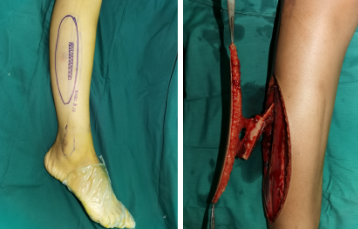

皮瓣术前照片

术中

术中,根据创面缺损的大小、形状设计皮瓣并划线标记,医生游离血管蒂长度满足受区要求、血供良好的皮瓣,移植到脚部的残损创面,在显微镜下细致吻合血管、神经。皮瓣供区则直接拉拢缝合,将来不会影响腿部的使用功能。